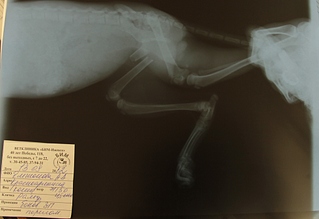

Из расходов - 3500 операция, 156,10 - антибиотики и шприцы (на эти суммы чеки выше я уже выкладывала), на постановку уколов и обработку спиц чеки я не просила выписывать, ездили в ветсервис, отдавали по 20 р. кажется, плюс два снимка по 300р. (от первого снимка чека точно не осталось, только сам снимок - выше тоже выложен, от второго снимка чек у брата, могу отсканить, но смысла думаю нет, траты все-равно перекрывают поступления).

Илона, я не знаю, какая стоимость операции со скидкой была бы, мы отдали сразу 3500. За консультацию первоначальную у Марины Викторовны с нас ничего не взяли, за снятие швов и последующие две консультации у Жуйкова тоже. Получается, что кроме операции мы заплатили только за два снимка, если ничего не путаю по 300 р. за каждый (ну за последний вот точно отдавали 300р.).